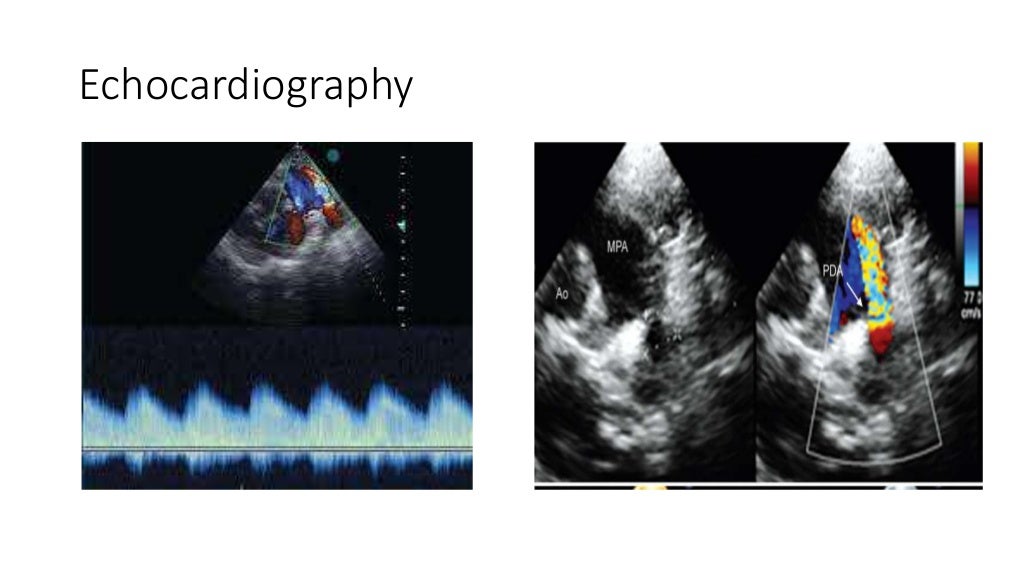

PDA Presentation Dr. Gaurav Agrawal Pda Case Presentation Patent ductus arteriosus (pda) is a congenital heart defect in which the ductus arteriosus, a vascular structure between the pulmonary. Patent ductus arteriosus (pda) accounts for approximately 5% to 10% of all congenital heart diseases. Ductal patency is a complication of extreme preterm birth [1]. Investigations confirmed moderate patent ductus arteriosus (pda) with heart failure and pneumonia. The patent ductus. Pda Case Presentation.